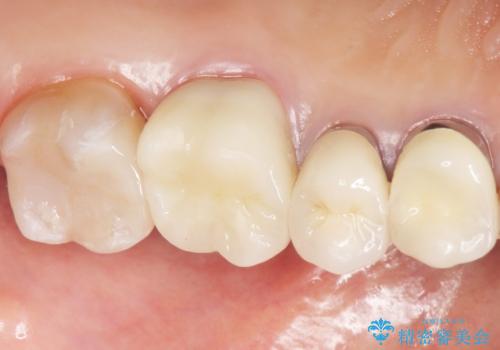

患者様のご希望により、左上6クラウン、左上7インレーによるセラミック治療を行いました。

クラウンの種類:オールセラミッククラウン スタンダード

インレーの種類:セラミックインレー(e-max press)